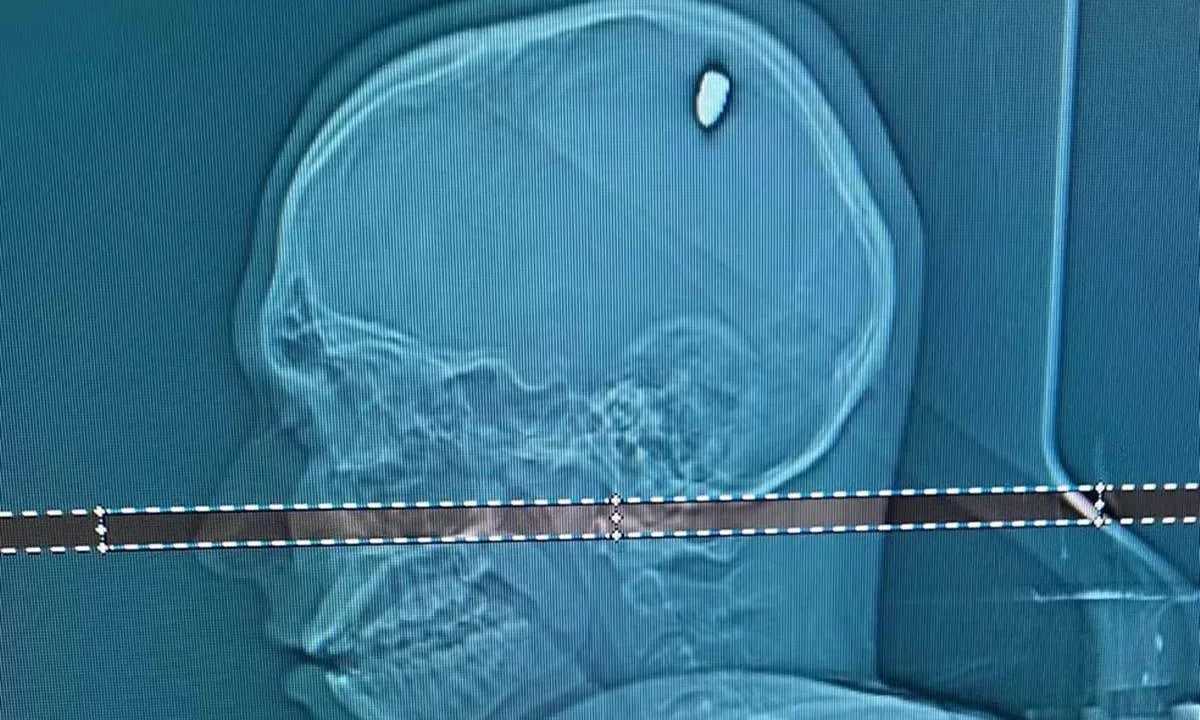

Um exame de tomografia mostrou que Mateus estava com uma bala alojada na cabeça. “Parte dela penetrou no cérebro. Isso causou compressão da região, e os movimentos involuntários do braço”, explica o neurocirurgião Flávio Falcometa.